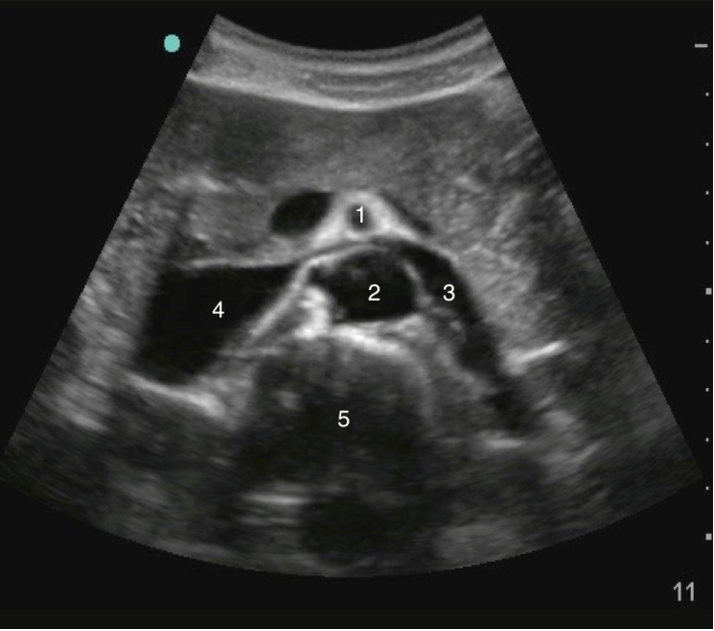

Aorta Transverse Proximal Image

1. Superior Mesenteric Artery (SMA)

2. Aorta

3. Left Renal Vein

4. Inferior Vena Cava (IVC)

5. Spine